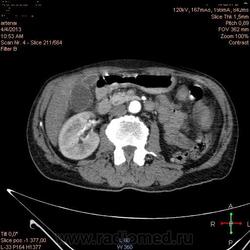

Здравствуйте, коллеги.Помогите разобраться.Пациент 1949 г беспокоять боли в животе , отсутствие аппетита, похудание .За неделю пожелтел, ослаблен.Нужно исключит кацер головки подж.железы.Анализы сегодня сдал еще не готовы.УЗИ зак увеличение л\узлов у ворот печени.Образов головки подж.железы ?На КТ жировой гепатоз.вроде головка подж железы не увеличены.

Мне надо исключить или поставить образование головки подж.железы.Хирурги ждут заключение, хотять оперировать.

А про билиарную гипертензию на УЗИ и КТ ничего не говорится?

Даже если вы пропустили малый рак панкреас, пациент умер не из-за него - желтуха не механическая, а, вероятней, паренхиматозная.